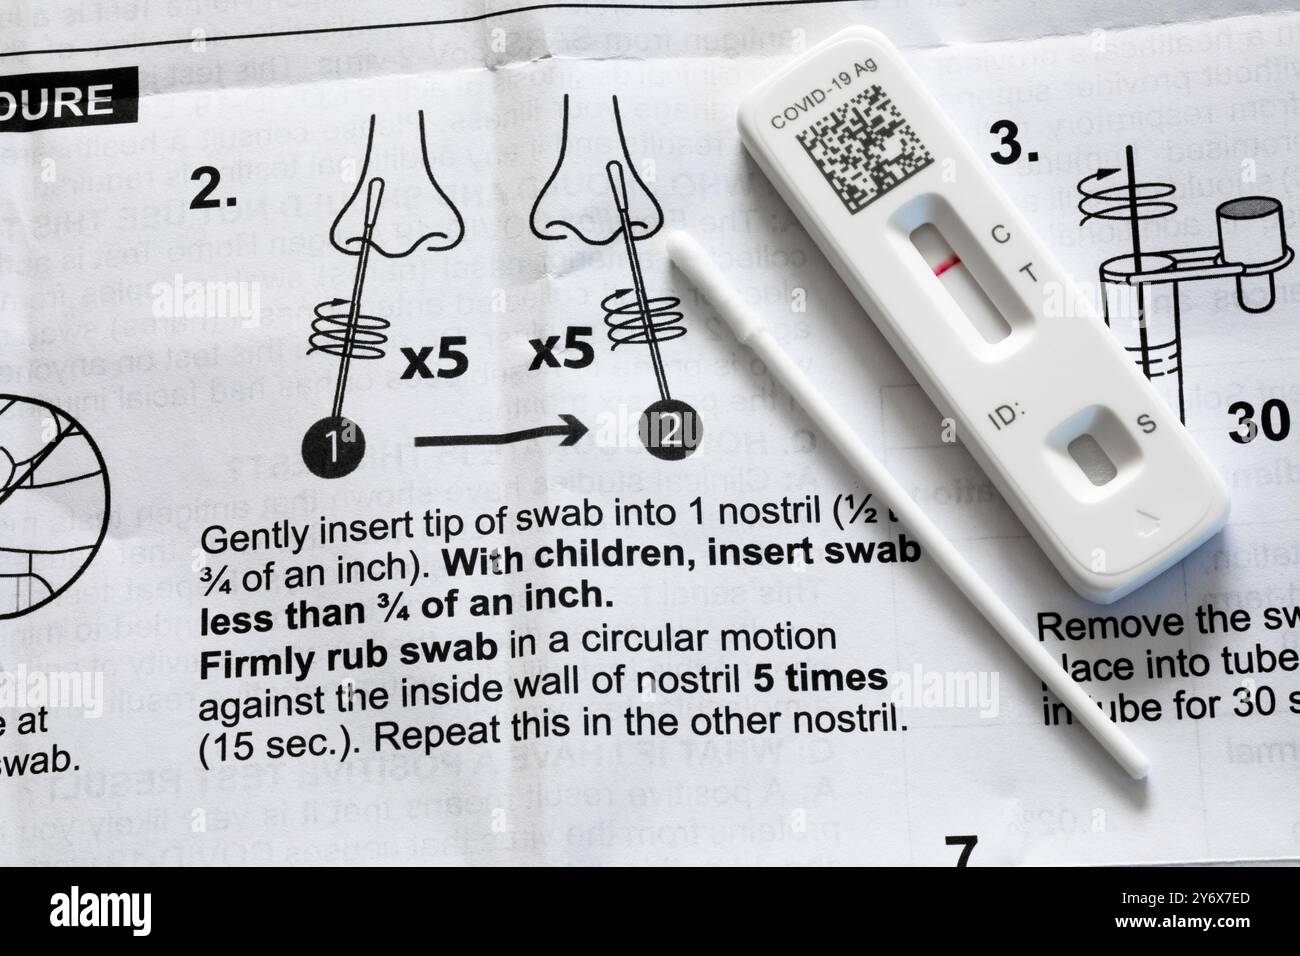

A medical, home covid test using antigen technology to check coronavirus antibody and keep people safe. Express health testing for covid 19 virus Stock Photohttps://www.alamy.com/image-license-details/?v=1https://www.alamy.com/a-medical-home-covid-test-using-antigen-technology-to-check-coronavirus-antibody-and-keep-people-safe-express-health-testing-for-covid-19-virus-image484480047.html

A medical, home covid test using antigen technology to check coronavirus antibody and keep people safe. Express health testing for covid 19 virus Stock Photohttps://www.alamy.com/image-license-details/?v=1https://www.alamy.com/a-medical-home-covid-test-using-antigen-technology-to-check-coronavirus-antibody-and-keep-people-safe-express-health-testing-for-covid-19-virus-image484480047.htmlRF2K45Y6R–A medical, home covid test using antigen technology to check coronavirus antibody and keep people safe. Express health testing for covid 19 virus

WA26118-00.....WASHINGTON - COVID-19 Antigen Home Test. Stock Photohttps://www.alamy.com/image-license-details/?v=1https://www.alamy.com/wa26118-00washington-covid-19-antigen-home-test-image623837829.html

WA26118-00.....WASHINGTON - COVID-19 Antigen Home Test. Stock Photohttps://www.alamy.com/image-license-details/?v=1https://www.alamy.com/wa26118-00washington-covid-19-antigen-home-test-image623837829.htmlRM2Y6X7ED–WA26118-00.....WASHINGTON - COVID-19 Antigen Home Test.